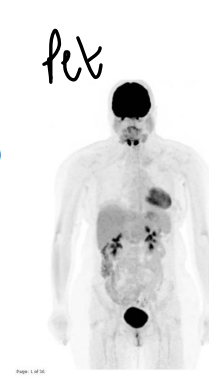

what are more complex tests used for diagnosis?

• positron emission tomography PET - patient injected with radio-labelled fluorodeoxyglucose 18F-FDG to identify metabolically active areas of the body (cancer cells as they will use up more glucose then other cells)

<ul><li><p>Computerised Tomography <strong>CT</strong> - 3D image using X-ray of chosen area</p></li><li><p>positron emission tomography <strong>PET</strong> - patient injected with radio-labelled fluorodeoxy<span style="color: purple;"><strong>glucose</strong></span> 18F-FDG to identify metabolically active areas of the body (cancer cells as they will use up more glucose then other cells)</p></li><li><p>PET-CT combination</p></li></ul><p></p>